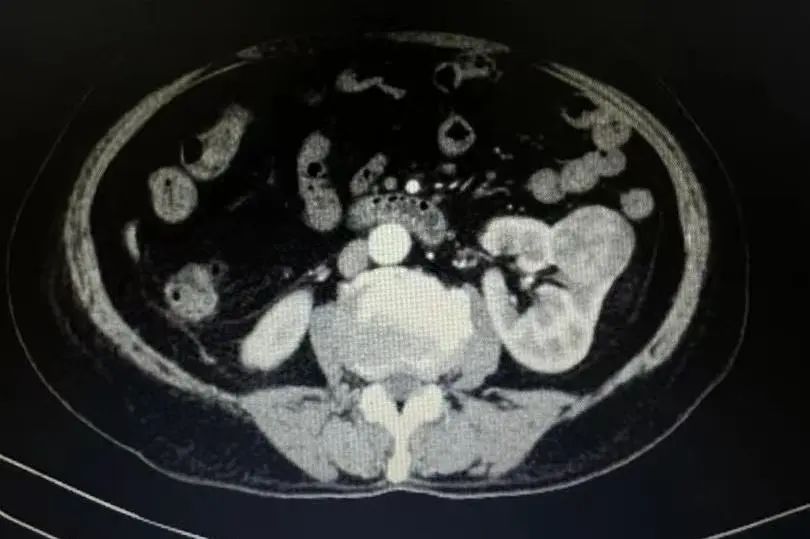

在凤凰医院住院后,详细检查显示右肾有直径约4厘米的肿物,考虑为肾脏肿瘤。面对这一情况,泌尿外科张锐主任深知李先生的家庭责任与生活压力。他和团队反复研讨,最终决定为患者实施“后腹腔镜下右肾部分切除术”,在切除肿瘤的同时保留肾脏,最大程度降低对患者生活的影响。

肾脏肿瘤保留肾脏手术有着严格的适应症,像TIa期肿瘤(肿瘤直径小于4厘米)、位于肾脏表面、孤立肾的肾癌、对侧肾功能不全或无功能肾者、双肾同时性肾癌等情况才适用。李先生的病情虽不完全符合典型指征,但凭借丰富的临床经验与精湛医术,张主任认为手术有成功的可能。

手术室内,无影灯亮起,张主任和团队全神贯注,每一个操作都精准无误。经过1小时50分钟的紧张奋战,成功完整切除肿瘤,李先生的肾脏得以保留。术后,医护团队精心照料,密切关注恢复情况。7天后,李先生顺利出院,又能重新回到工作岗位,继续为家庭拼搏。